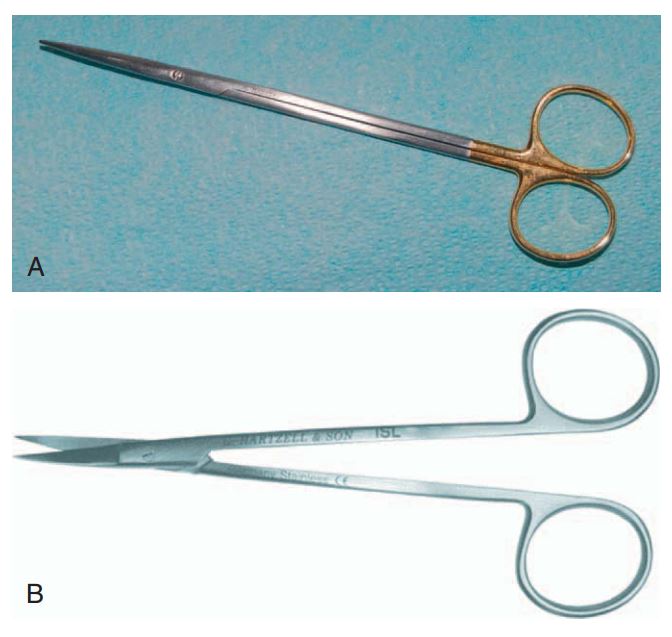

Kéo

Dùng để cắt hoặc tỉa mô. Kéo cắt chỉ (hay còn gọi là kéo Dean) thường có cán dài, ngón cái và ngón nhẫn đặt vào vòng cán, ngón trỏ đặt dọc theo trục kéo để giữ ổn định và hướng dẫn động tác. Không nên đặt ngón trỏ vào vòng ngón nhẫn vì như vậy thường khó kiểm soát. Kéo Dean có phần lưỡi tác dụng ngắn, sử dụng tốt để cắt chỉ trong lúc khâu và sau khi lành thương.

Một loại kéo khác là kéo Metzenbaum, hình dáng tương tự nhưng có phần mũi kéo tròn và cùn chứ không nhọn, chủ yếu dùng tỉa mô hoặc cắt mô.

Một loại kéo thứ 3 nữa là kéo Iris, nhỏ và mảnh, dùng nhiều trong phẫu thuật Implant (H2.15).